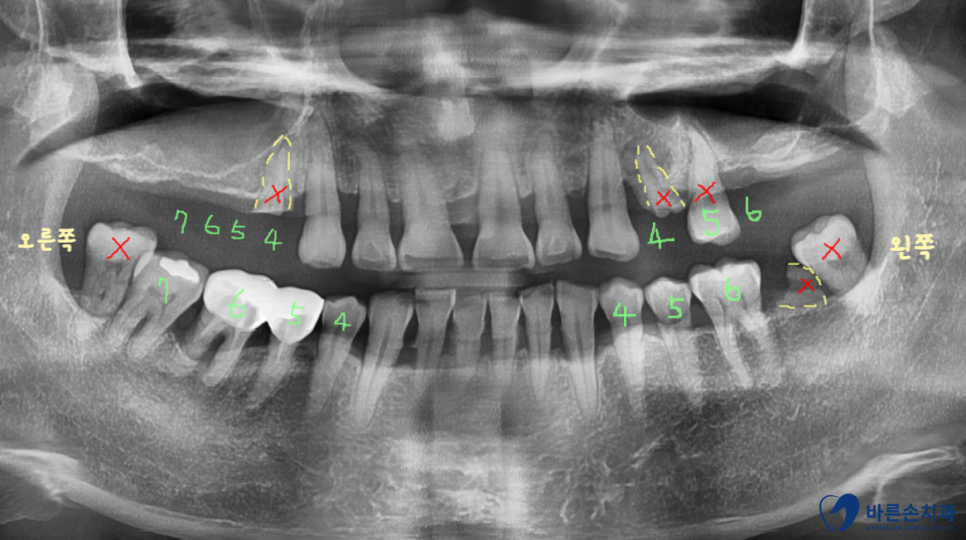

윗 어금니들이 다 빠지거나 부러진 환자분 께서 내원하셨습니다.

임플란트를 해야하는데 뼈가 없어서 안된다고 들으셨다고 오셨어요.ㅠㅠ

사진을 보시면 치아가 부러져서

작은 어금니는 뿌리만 남아있고

큰 어금니는 이미 상실되어있습니다..

구내 엑스레이 사진을 보면 양쪽 위 어금니들이

빠진지가 오래되어 상악동 함기화가 되어

임플란트 식립할 뼈가 부족합니다.

X 표시가 되어있는 치아는 발치하고

왼쪽은 치아 3개, 오른쪽은 치아 4개를 만들기로 계획을 세웁니다.

왼쪽도 원래라면 4개의 어금니가 전부 있어야 하지만

아래 맞닿는 치아 하나가 어차피 없기 때문에

3개까지만 제작하기로 했습니다.